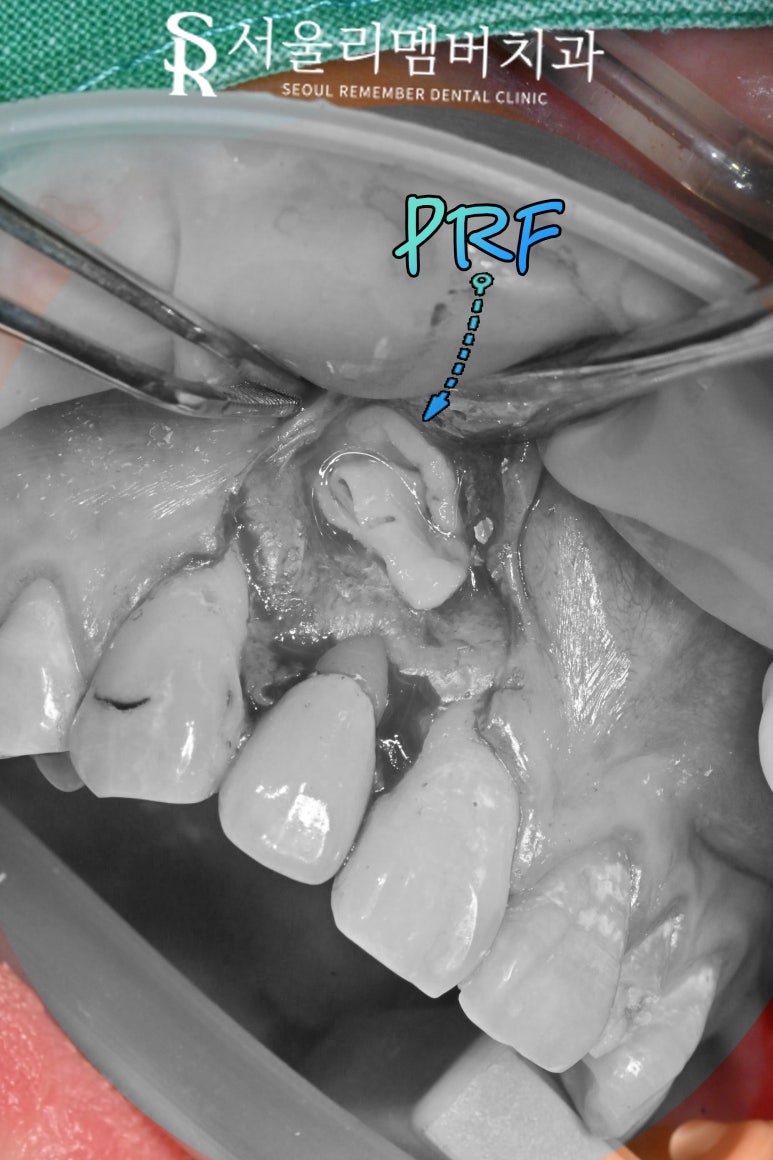

4단계: PRF 적용 및 봉합

2025.05.22

보라매 치과 에서

골이식 후 PRF 막을 덮어준 모습입니다.

PRF 막은 이식해둔 뼈를 보호하고

연조직이 골이식을 해둔 자리로

침투하는 것을 방지하는

차폐막 역할을 합니다.

PRF (Platelet-Rich Fibrin)

PRF는 혈소판뿐만 아니라

백혈구도 포함되어 있어

생체 친화적이며,

수술 부위를 보호하는

생물학적 막 역할도 수행합니다.